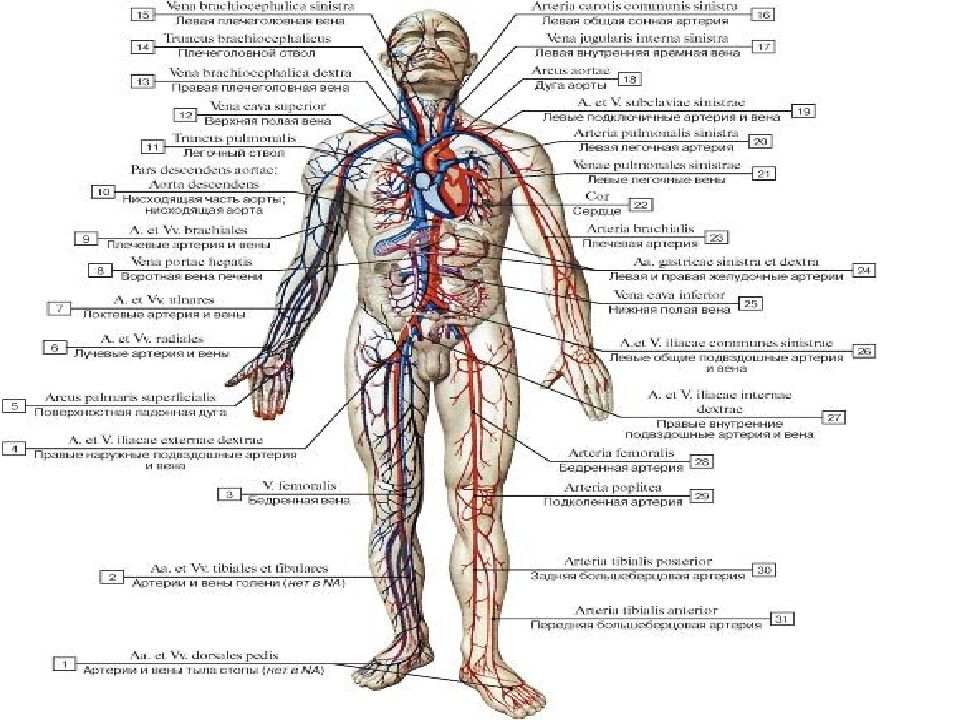

Анатомия человека: кровеносная система и её связь со скелетом